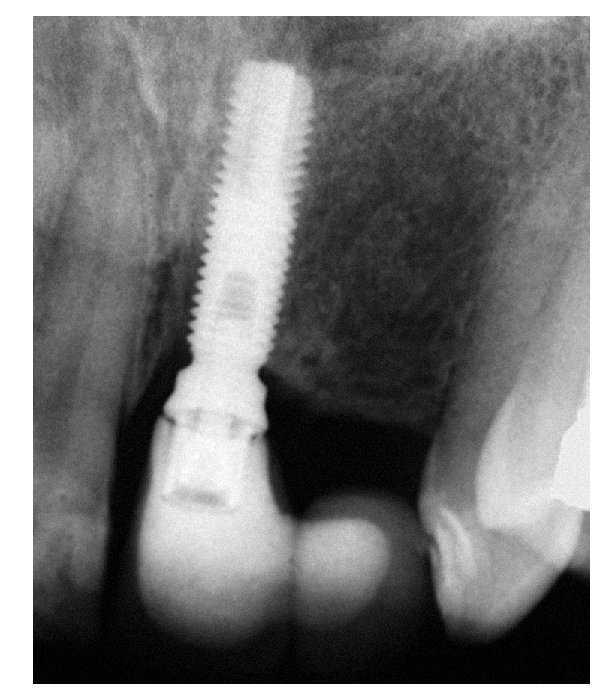

Figura 10. Radiografía periapical tomada 1 año después de haber colocado la prótesis definitiva. Puede observarse la presencia de cresta ósea en la región del incisivo lateral superior. La hendidura en el pilar de la prótesis es el resultado de un artefacto técnico debido a la angulación de los rayos X.

En las radiografías periapicales de los dos casos clínicos descritos en este artículo, se observaba un área radiolúcida circunferencial cerca de la plataforma de los implantes, compatible con la anchura biológica alrededor de los implantes de titanio11. Se han descrito diversos avances para mantener la cresta ósea alrededor de los implantes mediante modificaciones micro y macroanatómicas de los implantes19-21.